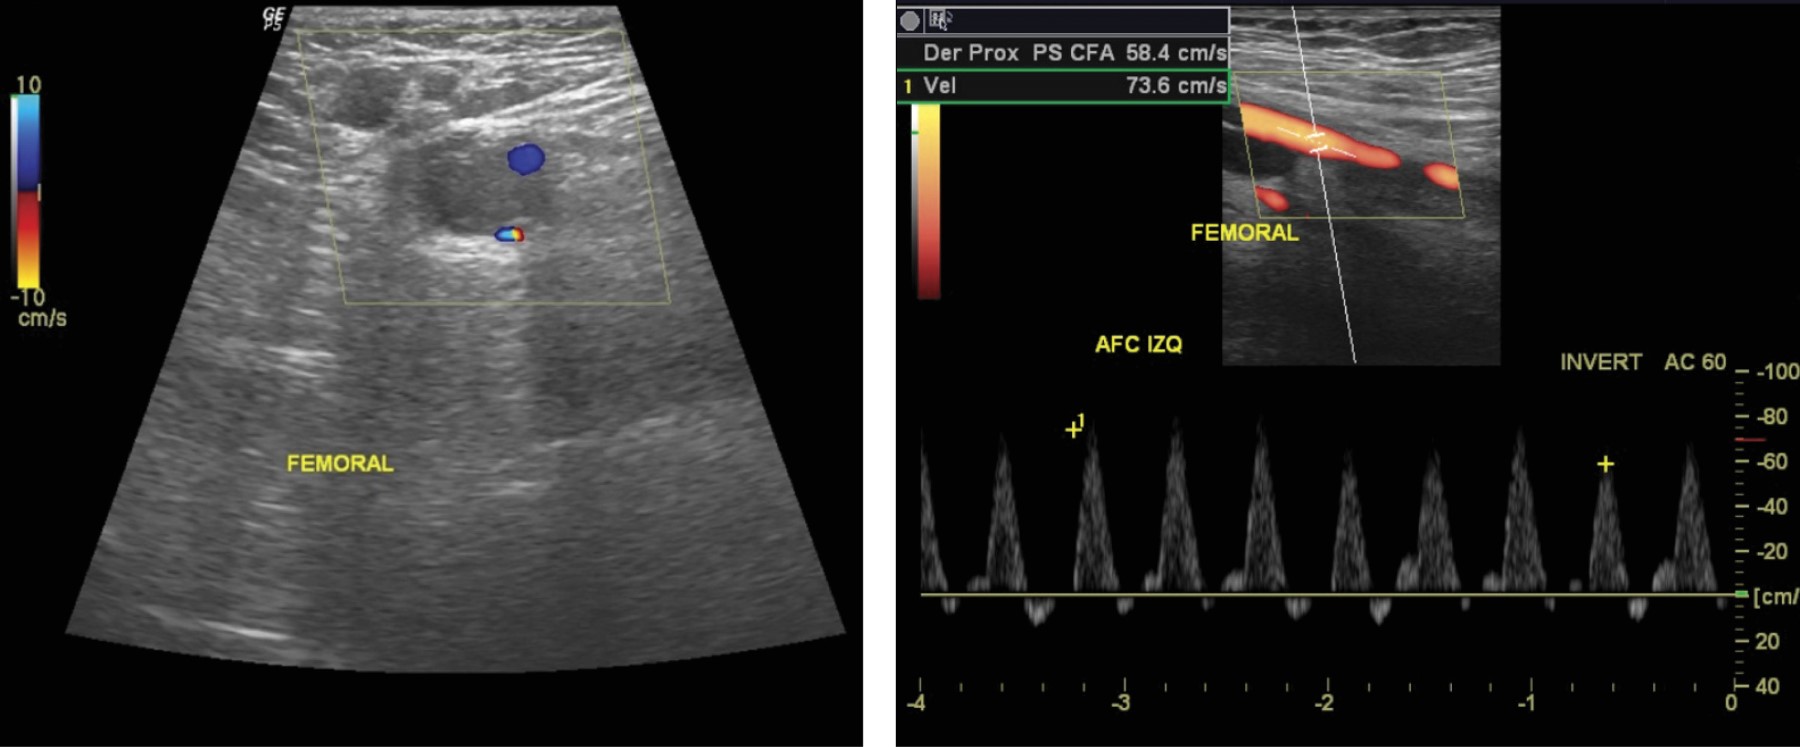

El análisis del electrocardiograma evidencia taquicardia sinusal sin otra alteración. Radiografía de tórax sin lesiones. Ante la sospecha de trombosis arterial se solicita ultrasonido Doppler de emergencia que reporta trombosis venosa profunda y superficial de miembro pélvico izquierdo, arteria iliaca externa permeable, arteria poplítea izquierda presentando flujo en su interior, no audible y sin espectro Doppler (Figura 2). Se realiza angiotomografía contrastada que evidencia edema de tejidos blandos, disminución del calibre de arteria femoral del lado izquierdo en tercio medio y distal, sin paso de contraste a partir de la arteria poplítea, trombosis venosa superficial y profunda en extremidad izquierda, extremidad derecha sin alteraciones (Figura 3). Tomografía de cráneo sin evidencia de patología (Figura 4). Inicia manejo con anticoagulación (enoxaparina), pentoxifilina, terapia hídrica con soporte con aminas vasoactivas (adrenalina y dobutamina) y antibiótico de amplio espectro (ceftriaxona), además de transfusión de hemoderivados e ingreso a Unidad de Terapia Intensiva Pediátrica.